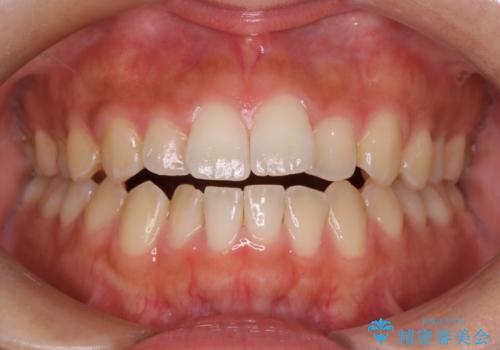

【非抜歯】インビザラインで正しい噛み合わせを

【非抜歯】インビザラインでガタつきと口元を改善!非抜歯でも印象が変わる矯正治療